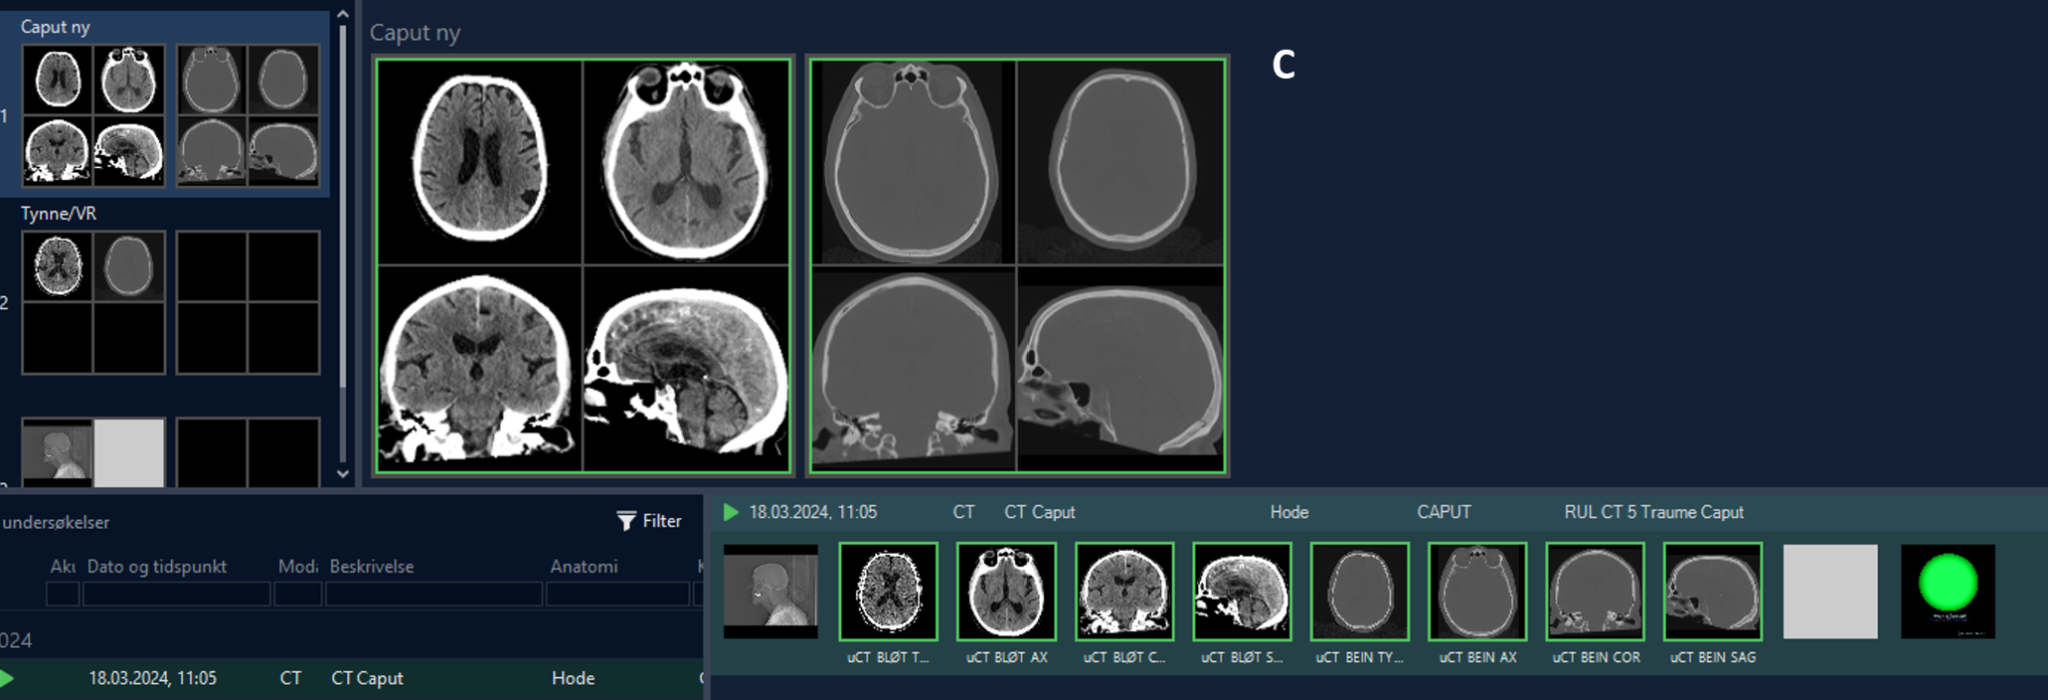

Over a 3 month period (from 1 June to 31 August 2024), all patients with suspected TBI and stroke patients who underwent a head CT were included in this study, and were approved by the regional ethics committee (REK 324897). Radiologists and radiographers from Oslo emergency department and Oslo University hospitals were instructed to “push” images from PACS to the NeoMedSys platform (details below). CT images came from 6 different CT scanners (Simens and GE) and were pushed to NeoMedSys as DICOM files and tagged digitally by the frontline user and processed using the VIOLA-AI model (details below) within NeoMedSys. Results of the analysis were presented as an automated VIOLA-AI report presented back in PACS consisting of a binary mask demarcating the ICH and its volume and a green circle when an ICH was not detected(Figure 1-a).

Demographic data were retrieved, including the time when: 1) CT was performed, and 2) the radiologist signed the report. Two patient groups were created based on whether an ICH was detected or not. Within the ICH detected group the clinician further classified the bleed etiology as being: epidural hematoma (EDH), acute subdural hematoma (SDH), subarachnoid hemorrhage (SAH), intraparenchymal hematoma (IPH), or intraventricular hematoma (IVH), as well as evidence of mass effect (Figure 1-b). As this was a live consecutive patient population other pathologies were also encountered and were classified as non-ICH with other pathologies i.e., tumor, non-hemorrhagic stroke, etc. All information was retrieved from PACS and the signed radiology report (Figure 1-c).